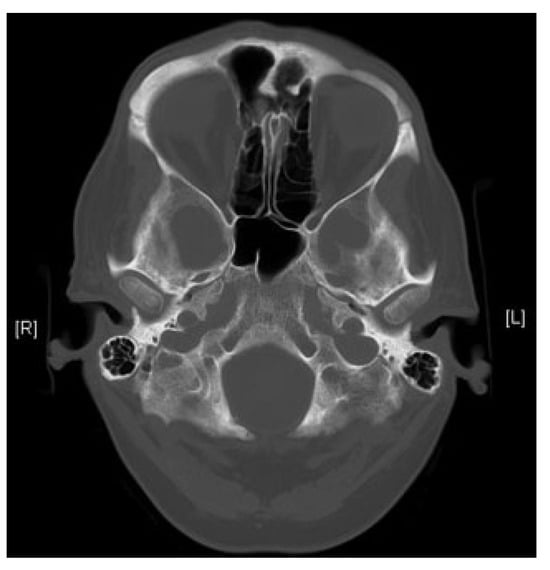

A CT scan of the brain and orbits was performed. This was difficult to interpret because of the metallic artifact from the foreign body. The scan showed the right wing of the brass statuette penetrating the medial aspect of the right orbit and entering the middle and posterior right ethmoid sinuses (Figure 2). It was difficult to ascertain whether the injury had extended to the anterior cranial fossa. There was no evidence of intracerebral hemorrhage or air.

Figure 2. Preoperative computed tomography head image.

On endoscopic examination, the injury had penetrated the lamina papyracea, through the right ethmoid sinuses reaching the dura. The dura had not been breached and there was no CSF leak. There was a 5 × 5 mm area of exposed dura which was left alone. An uncinectomy and anterior ethmoi-dectomy was performed. A corrugated drain was inserted with the tip sitting next to the defect in the lamina papyracea and sutured to the nasal septum. Inpatient management continued for a further 7 days with intravenous antibiotics. The drain was removed on the second postoperative day. Initial visual acuity was 6/60 for the right eye with a relative afferent papillary defect. The left (uninjured) eye had visual acuity of 6/6. Postoperative CT scan was performed (Figure 3) showing only a defect in the lamina papyracea. This patient made a good recovery with no CSF rhinorrhea or infection postoperatively. He was followed up by ophthalmologist only on the grounds that there was no CSF leak and no skull base or ethmoidal injury. As such any ENT or neurosurgical follow-up was not indicated. He was followed up for 1 month and subsequently 6 months and then 1 year following the injury. Visual acuity remained 6/60 in the injured eye and 6/6 in the contralateral eye.

Figure 3. Postoperative computed tomography head image.